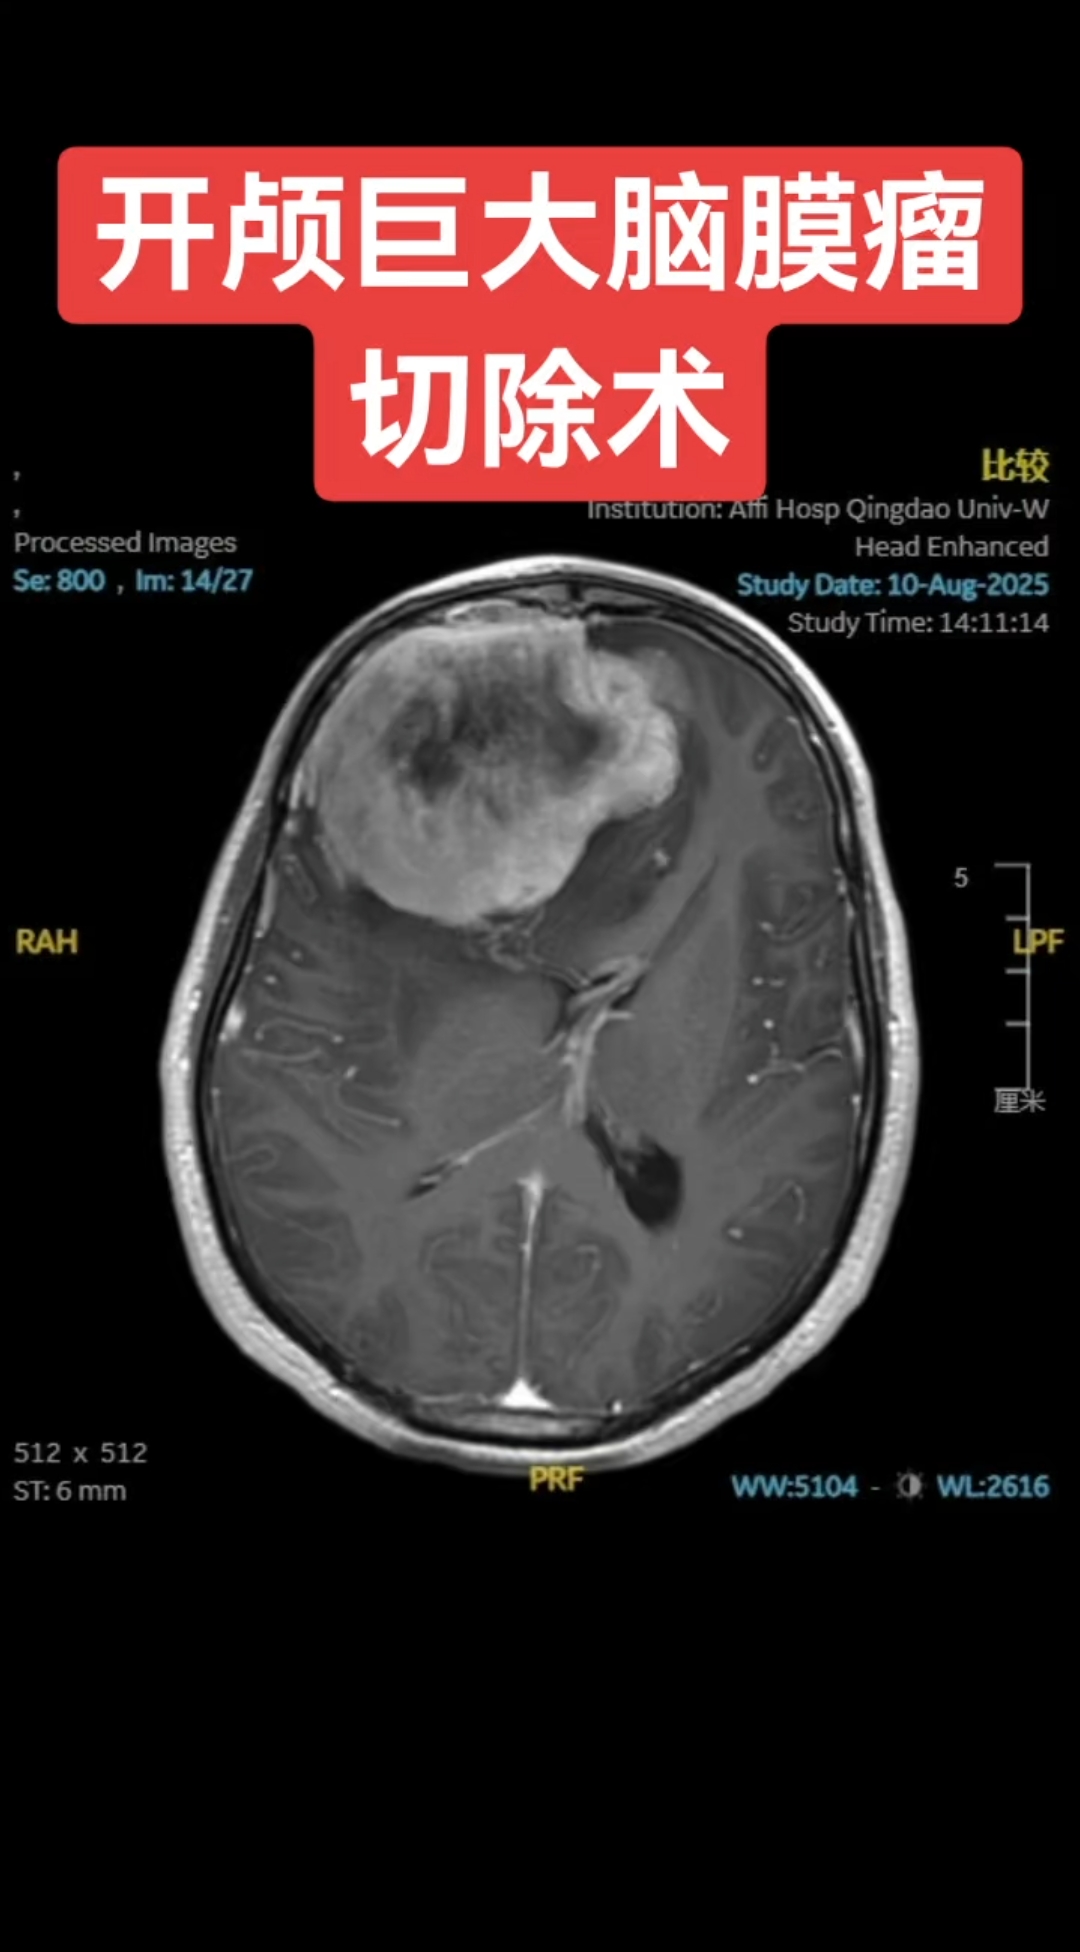

脑膜瘤手术是大手术,因为脑膜瘤是颅内的病灶,所以要开颅,开颅都是大手术,相对其他手术来讲,因为别的手术不用开脑袋,把脑袋打开,颅骨钻个孔,然后再去做脑膜瘤的手术脑膜瘤手术能够切除脑膜瘤,因为脑膜是在最外层,在颅内手术里是相对比较简单的,但是脑膜一定要多切一些,因为脑膜瘤可能会沿着。

脑膜瘤手术通常需要开颅,但在特定情况下可以考虑非开颅治疗1 开颅手术 主要治疗方式开颅手术是脑膜瘤的主要治疗方式之一,特别是对于大多数脑膜瘤患者,开颅手术可以切除肿瘤,达到治愈的目的 适用情况当脑膜瘤位置相对表浅,与周围组织结构粘连不紧密时,开颅手术是首选的治疗方案2 非开颅。